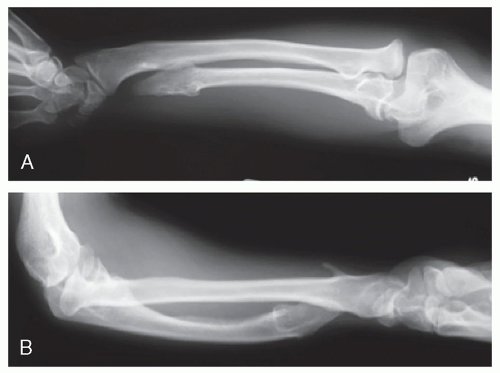

Severely maligned forearm with dislocated radial head proximally and distal radioulnar joint (DRUJ) at wrist (Figure 12.1)

![]() Figure 12-1 ▪ Anteroposterior (AP) (A) and lateral (B) radiographs of chronic forearm deformity from osteochondromatosis with dislocated radial head at elbow and distal radial-ulnar joint at wrist. |